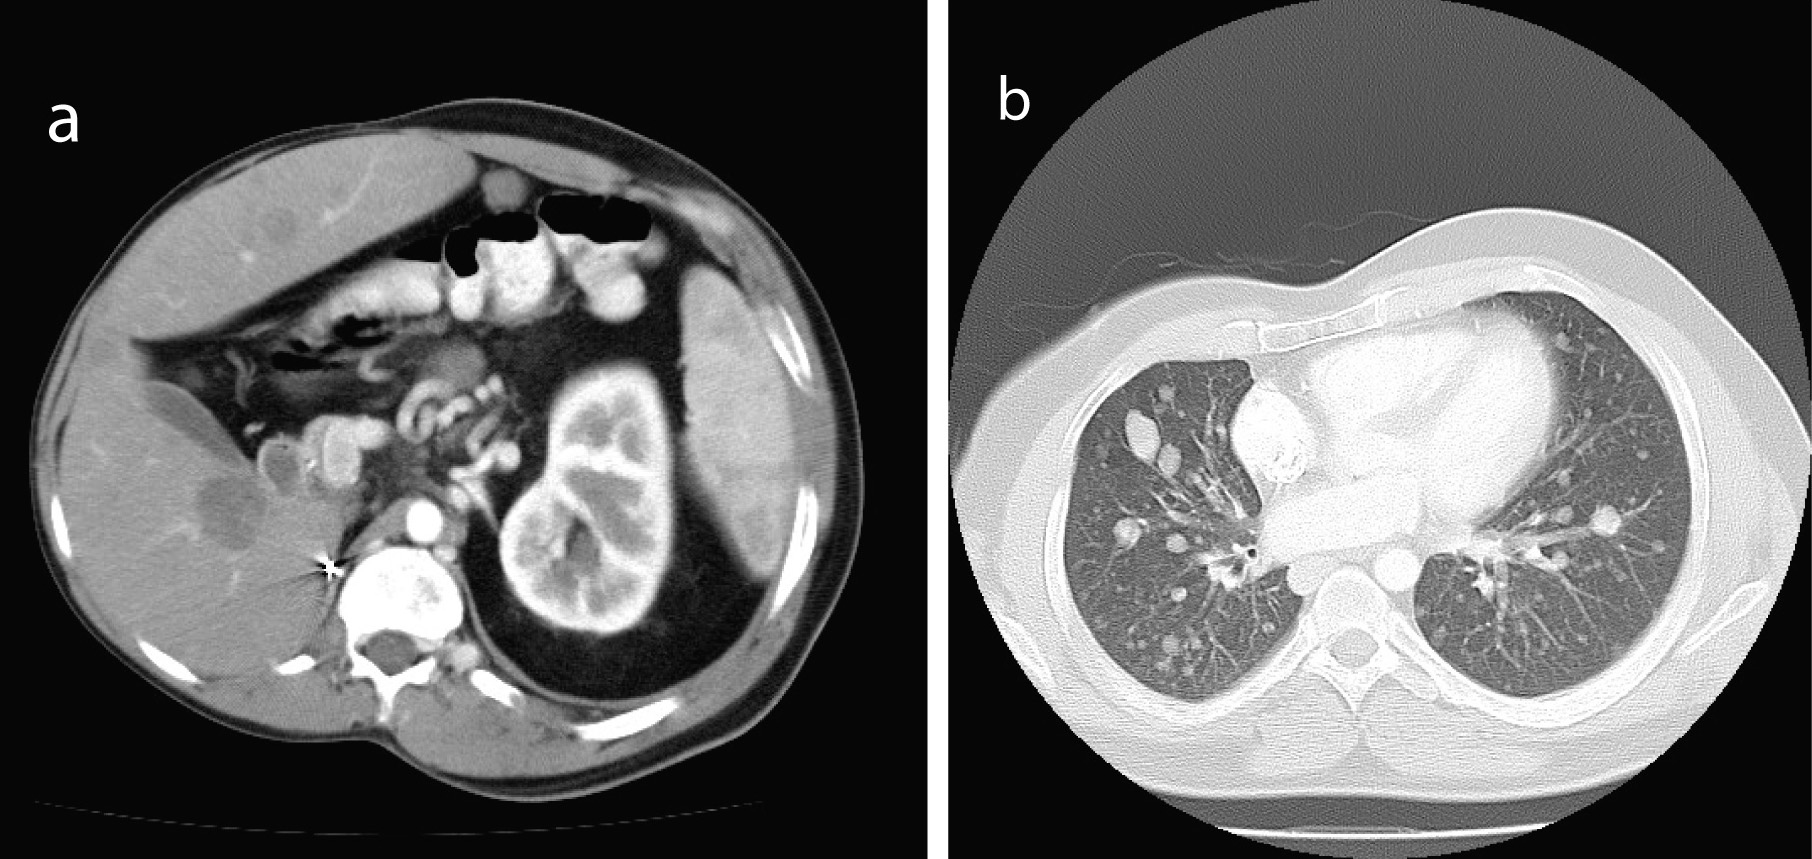

In early 2008 at age 35, the patient noticed a right axillary lymph node. He was assessed by a surgeon in April 2008. There was a plan for monitoring this with review again in August 2008 at which time it was still present. A submental node had also developed in the intervening time. He was booked for an excision biopsy but he presented to his local doctor with right upper quadrant discomfort in September 2008. CT scan showed a 39 x 71 mm retroperitoneal mass in the right para-aortic region in the field of his previous radiotherapy. It also showed multiple liver lesions, pulmonary nodules, and lymphadenopathy. He was then referred to Cancer Clinic for further investigation and management.

When first seen at the Cancer clinic, he appeared to be a pleasant, average built man with extensive scoliosis of his spine. He had an enlarged liver and axillary and submental lymphadenopathy. He underwent an excision biopsy of the axillary node. Histopathology was consistent with leiomyosarcoma, with well encapsulated, moderately pleomorphic and mitotically active smooth-muscle tumor. Desmin stain was positive and smooth muscle actin stain showed patchy positivity; AE1/AE3, S100 and C-Kit and EBER were all negative. Staging CT scans were performed which showed multiple metastases (Fig. 1). A staging positron emission tomography-CT scan showed uptake in the para-aortic region, the liver, a nodule inferior to the spleen, a nodule anterior to the proximal right latissimus dorsi muscle and variable uptake in the pulmonary nodules (Fig 2). The investigations confirmed a diagnosis of RIS of LMS subtype, with dominant mass in the previous radiotherapy site and extensive metastases almost three decades after his initial treatment. He was offered palliative chemotherapy, but he declined and went onto having various alternative therapies and finally succumbed to his cancer nearly 12 months after the diagnosis.

![]() Click for large image | Figure 1. Staging CT showed multiple metastases (a, b). |